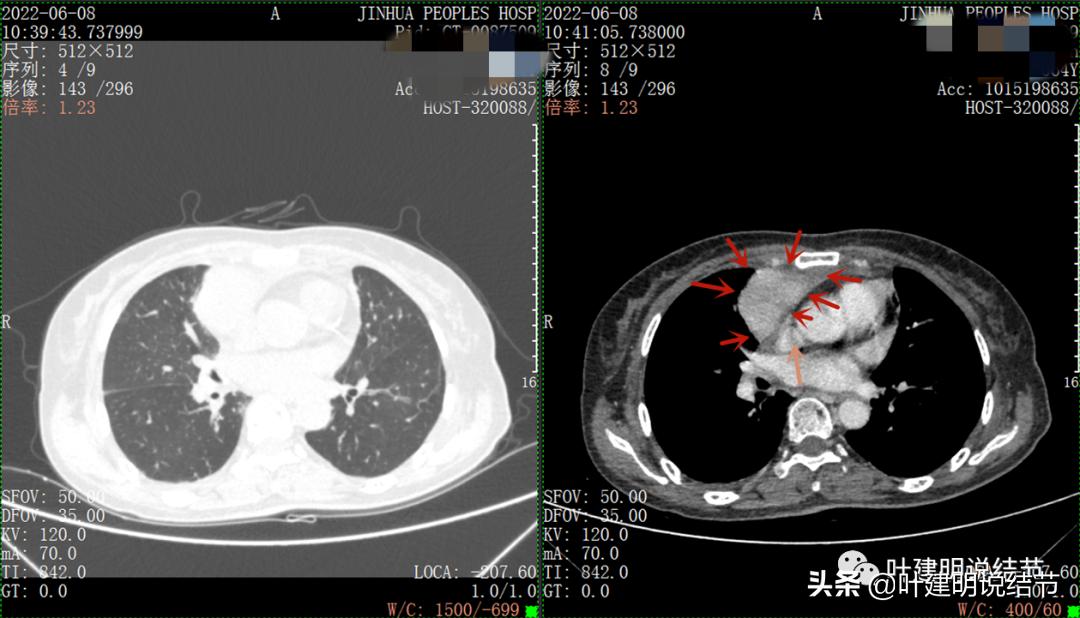

以下图片左侧是肺窗,右侧是纵隔窗。红色箭头示病灶,桔色箭头示无名静脉,黄色箭头示支气管,砖色箭头示上腔静脉,蓝色箭头示主动脉,紫色箭头示肺动脉。

病灶占据前纵隔从上到下全程,多中心,密度不均,对心脏与大血管有压迫,没有明显侵犯

病灶表面不平,中间有坏死

上图示最大横断位达5厘米